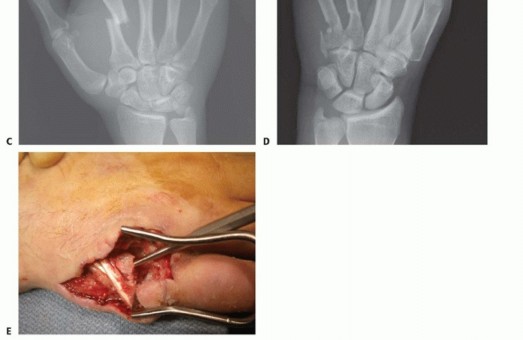

TECH FIG 4 • A-C. Patient with torsional injury to long and ring fingers leading to spiral fractures of the third and fourth metacarpals. The combined injury made it possible for malrotation to develop. D.

TECH FIG 4 • (continued) G,H. Motion at 6 weeks after surgery. The periosteum is elevated at the fracture site to assist with assessment of fracture reduction. As much of the interosseous muscle is left attached to the metacarpal as feasible to preserve blood supply to the bone.The fracture is reduced and provisionally stabilized with reduction clamps (TECH FIG 4D).

LAG SCREW FIXATION

Long oblique and spiral fractures whose lengths are at least twice the diameter of the bone at the level of the fracture are amenable to limited fixation with screws only (see TECH FIG 4A-C).Appropriately sized lag screws (1.4 to 2.7 mm) are placed. Typically, two or three screws are used (TECH FIG 4E,F).The first screw is placed perpendicular to the fracture in order to compress it and the second screw is placed perpendicular to the bone to resist longitudinal forces.In order to get proper compression with a lag screw construct, it is important to overdrill the near cortex.When using a 2.0-mm screw system, a 1.5-mm drill bit is used to drill both cortices. The near cortex is then overdrilled with a 2-mm drill bit.A countersink is used to maximize contact between the head of the screw and the bone. The size of the screw is measured and an appropriately sized screw is placed.The periosteum and interosseous muscle fascia are reapproximated to cover the screws. The juncturae tendinum are repaired and the skin is closed in standard fashion.The hand is then immobilized with the MP joints flexed 70 to 90 degrees with a forearm-based splint. Early motion can be started as early as 4 to 7 days, depending on fracture stability (TECH FIG 4G,H).

TECH FIG 7 • A,B. Coronal intra-articular fracture that extends to the metacarpal neck. C,D. If there is no comminution, the fracture can be addressed through a volar approach and stabilized with lag screws.